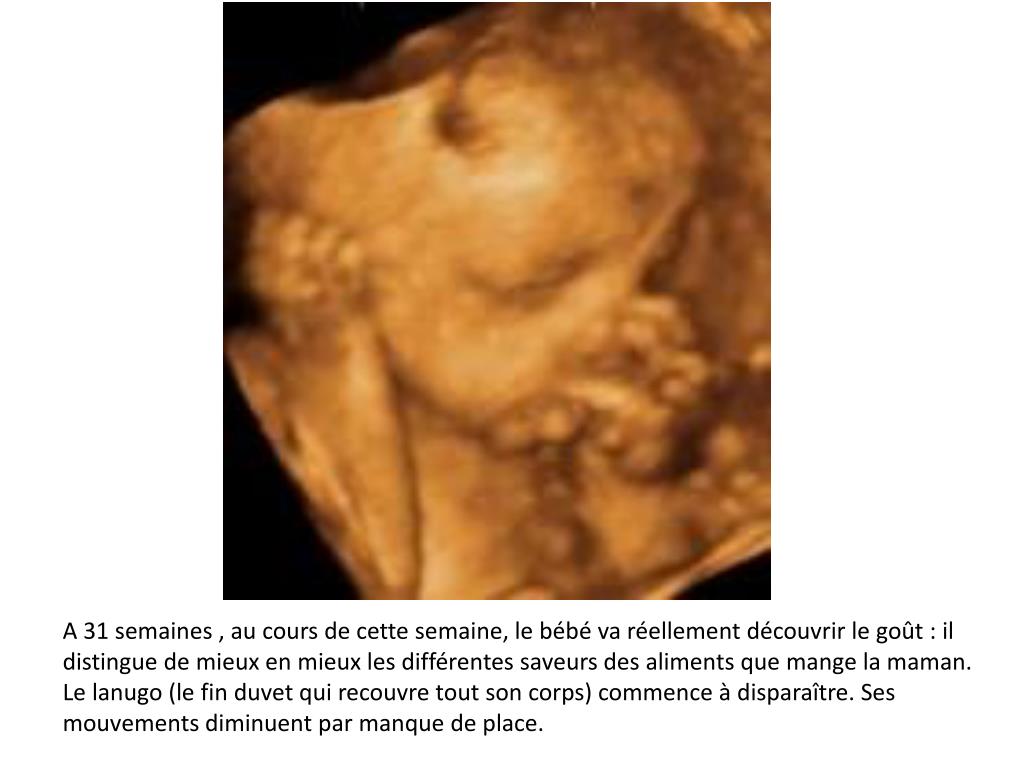

Le futur bébé pèse 1,7 kg pour 39 cm et se prépare pour la sortie Il se recroqueville en ayant les genoux repliés, les bras et les jambes croisés avec un menton ramené vers la poitrine Il occupe quasiment toute la place dans la cavité utérine Il grandit lentement, mais grossit rapidement et se sent à l'étroit dans la poche amniotique Disparition inquiétante Marion Disparue le 14 novembre 1996 à l'âge de 10 ans Marion Wagon Agen (), LotetGaronne En cas d'information, contacter le 01 40 97 80 16 Tweet Disparition inquiétante Charazed Disparue le 8 juillet 1987 àD'autres changements mineurs incluent la disparition progressive du lanugo Cette fine couche de cheveux qui aide à réguler la température en raison du peu de graisse sous la peau du bébé A la naissance, vous pouvez voir des restes du lanugo